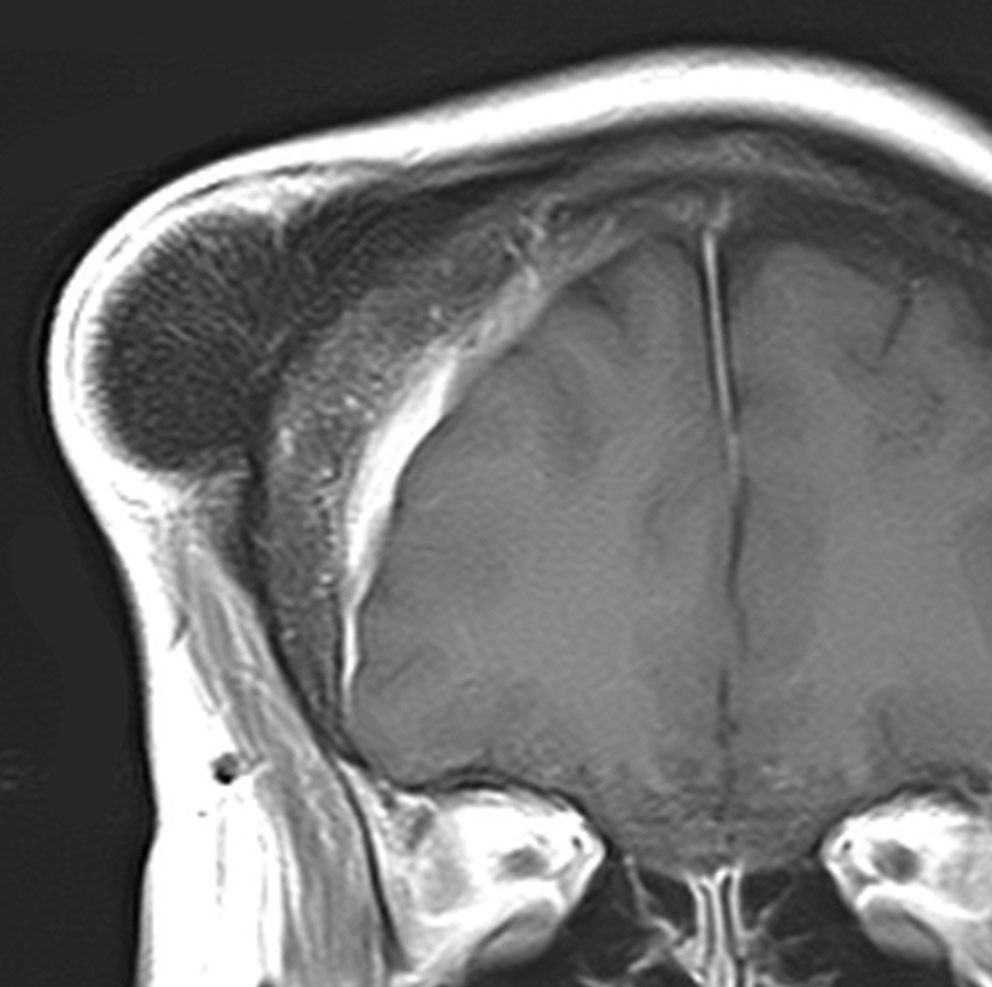

骨内髄膜腫 osseous meningioma

骨内増殖をする髄膜腫です。頭蓋骨腫瘍と間違えるようなものです。触った感じは骨腫ですが,CTでは,表面が毛羽立っていて,頭蓋冠に浸潤していることが特徴です。浅側頭動脈からの豊富な血流があります。

わずかですが頭蓋内にも腫瘍があり,硬膜が肥厚してガドリニウム増強されます。

頭蓋骨をかなり広範におかすので骨は捨てません。開頭して取り外した骨の厚くなっている部分と髄膜腫で軟らかくなっている部分を削除して,それから骨片をオートクレーブで短時間熱処理して,元あった所にもどします。下の画像は手術後1年半が経過したものですが,髄膜腫の再発はなく,熱処理骨弁は吸収されないで生着しています。